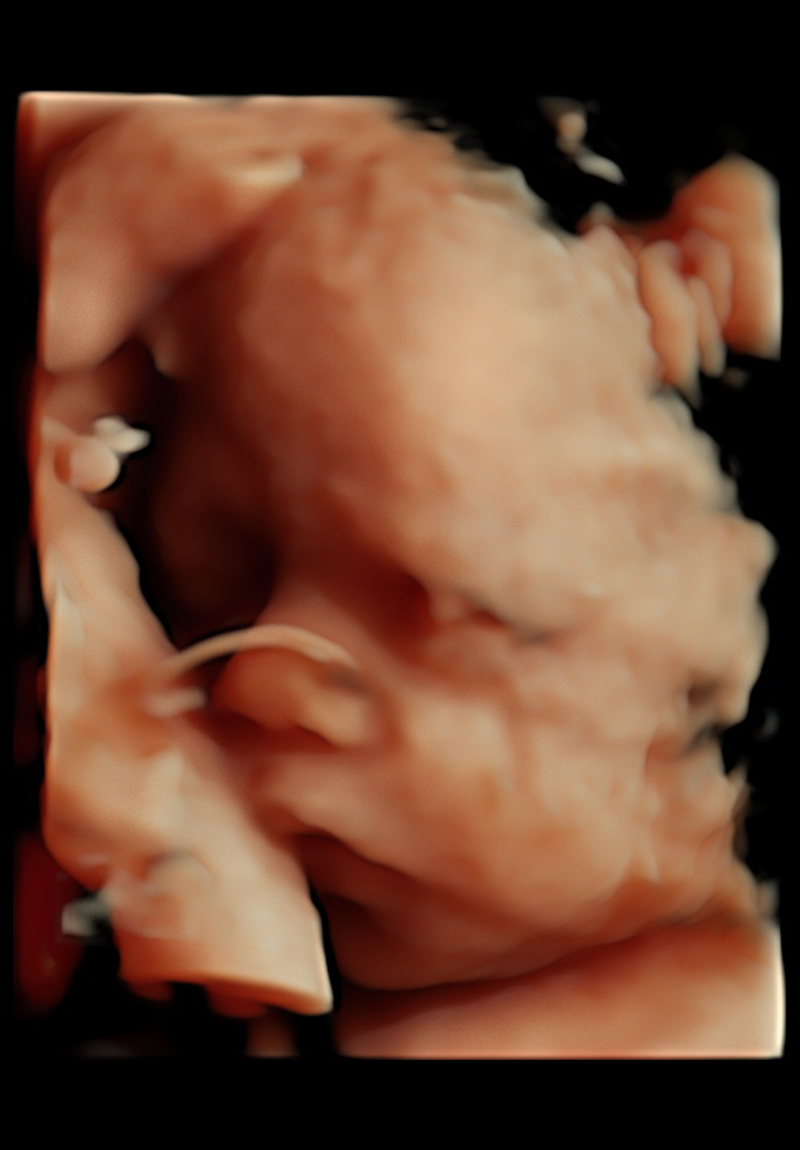

Eco Anatómico 4D

Realizado entre las semanas 20 y 30, el Eco Anatómico 4D, es un estudio que permite una valoración detallada del crecimiento, órganos y estructuras de bebé. Este eco es crucial para la detección temprana de malformaciones congénitas. Si la posición de bebé y las condiciones nos permiten, podemos llevarnos un hermoso recuerdo al tomar fotografías en 4d.